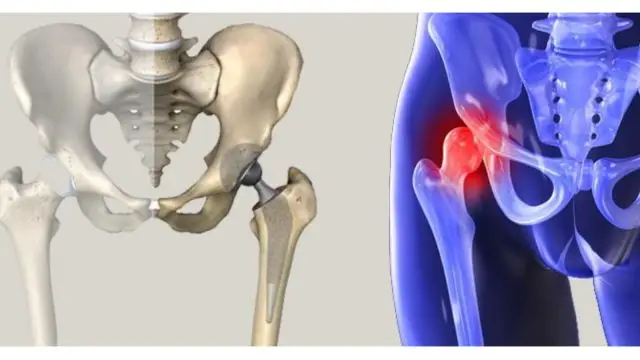

Kalça Anatomisi ve Minimal İnvaziv Kalça Protezi

Kalça eklemi, vücudun en büyük ve en fazla yük taşıyan eklemlerinden biridir. Femur başı (uyluk kemiği topu) ile asetabulum (pelvis soketi) arasında yer alan bu eklem, top-soket yapısı sayesinde hem sağlamlık hem de geniş hareket kabiliyeti sağlar. Eklem yüzeyini kaplayan eklem kıkırdağı, kemiklerin birbirine sürtünmeden hareket etmesini sağlar. Ayrıca, kalça

Total Eklem Değiştirme Cerrahisi Nedir?

Total eklem değiştirme cerrahisi, diğer adıyla eklem protezi ameliyatı, ileri derecede kalça veya diz ağrısı yaşayan hastalarda uygulanan en etkili tedavi yöntemlerinden biridir. Bu ameliyatın temel amacı; eklemdeki hasarlı veya aşınmış yüzeyleri yapay implantlarla değiştirerek, ağrıyı azaltmak, hareket kabiliyetini geri kazandırmak ve yaşam kalitesini artırmaktır. Eklemdeki kıkırdak doku yıllar içinde